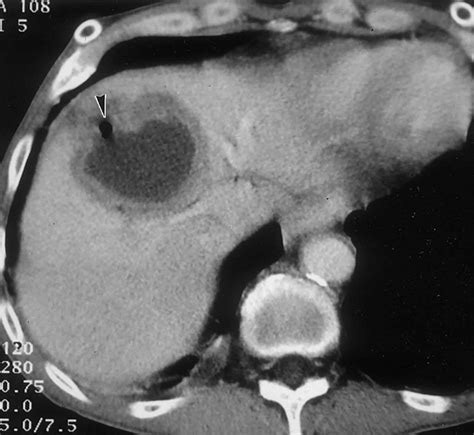

• Computed Tomography (CT) Scan: A CT scan provides detailed images of the liver and can help determine the size and location of the cyst.